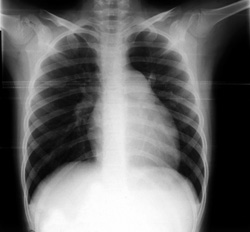

Εργαστηριακός έλεγχος: Α/φία θώρακα: προβολή του κώνου της πνευμονικής αρτηρίας

και ελαττωμένη αιμάτωση στην περιφέρεια των πνευμόνων (εικόνα 1).

Eικόνα 1. Ακτινογραφία θώρακα της ασθενούς κατά την εισαγωγή.

Προβολή του κώνου της πνευμονικής αρτηρίας και ελαττωμένη αιμάτωση στην περιφέρεια

των πνευμόνων.